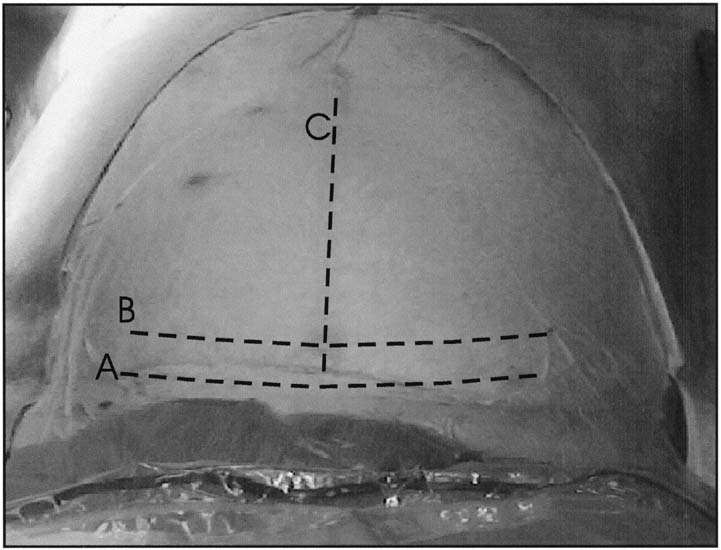

Uterine Incisions

There are three standard uterine incisions that can be performed for delivery of the fetus: low transverse, low vertical, and classical (Fig. 4). The specific type of uterine incision should be determined by the primary surgeon at the time of the operation based on gestational age and lie of the fetus and any uterine anomalies.

Fig. 4. Uterine incisions. A. Low-transverse uterine incision should be made through the thin, noncontractile portion of the lower uterine segment in a curvilinear fashion. Also pictured is a low-vertical incision, which is made through the noncontractile lower uterine segment in a vertical fashion. B. J-extension of the low-transverse incision. When additional exposure to the uterine cavity is required to deliver the fetus, the low-transverse incision can be extended laterally and cephalad to increase the length of the incision without endangering the uterine arteries. C. Another option in this situation is to use a T-extension in the midline. D. The classical uterine incision is made through the contractile portion of the myometrium above the bladder reflection.

The standard low-segment transverse incision accounts for 90% of all uterine incisions.28 It is initiated sharply in the lower uterine segment, perpendicular to the long axis of the uterus. This incision is made sharply with the scalpel in the midline and performed down to the level of the fetal membranes, with care being made not to incise the membranes. This incision is then extended laterally using either blunt dissection with the fingers or bandage scissors (Fig. 5). There was thought to be no difference between the two methods in amount of blood lost or in the rate of extension of the incision into the lateral uterine vessels when they were compared and correlated by the stage of labor.36 However, a recent investigation revealed a greater risk of subsequent blood transfusion in woman whose incision was extended sharply compared to those extended bluntly.37 When blunt dissection is used, an upward curve of the incision may be created by the surgeons placing their thumbs on the patient's anterior superior iliac spines and index fingers in the uterine incision. By keeping the hand in this position, the incision is pulled open in an arc.

Fig. 5. Extension of the lower uterine incision may be accomplished either by inserting fingers into the uterine cavity and bluntly stretching the myometrial incision in a curvilinear fashion or by sharply cutting the lower uterine segment with bandage scissors. When the uterus has a poorly developed lower uterine segment, using bandage scissors is often preferable.

Intentional extension of the low-transverse incision is necessary in 1% to 2% of cases.38 Typically, the extension of the low transverse incision is performed by creating a low vertical incision in the midline, T-ing the uterine incision, or creating a vertical incision at the lateral aspect of the uterine incision, a J-extension. These extensions are commonly performed for malpresentations, poorly developed lower uterine segment, or deep transverse arrest.38 When performed, extensions of the low-transverse incision are associated with increased incidence of maternal blood loss, broad ligament hematoma, and uterine artery laceration compared with low-segment transverse incisions that do not require extension.

The low-vertical uterine incision is made parallel to the longitudinal axis of the uterus in the midline, with care being taken to remain below the contractile portion of the uterus and within the thin lower uterine segment. Other than the direction of the incision, technical aspects are carried out as described for the low-transverse uterine incision. Studies have shown that there is no increased risk of uterine rupture in patients with this type of incision compared with the low-segment transverse incision as long as the incision remains primarily in the thin lower uterine segment.39

A classical uterine incision is made by incising the uterus parallel to the longitudinal axis of the uterus through the contractile portion of the myometrium. Indications for classical uterine incision include situations in which the lower uterine segment is not adequately developed to accommodate a low-transverse or a low vertical incision; cases of abnormal fetal lie such as back-down transverse lie, in which the low-transverse or low-vertical incision will not allow the operator adequate access to the fetus for manipulation and delivery, or when myomas or uterine abnormalities distort the uterus in such a way as to make a low transverse incision inadvisable.